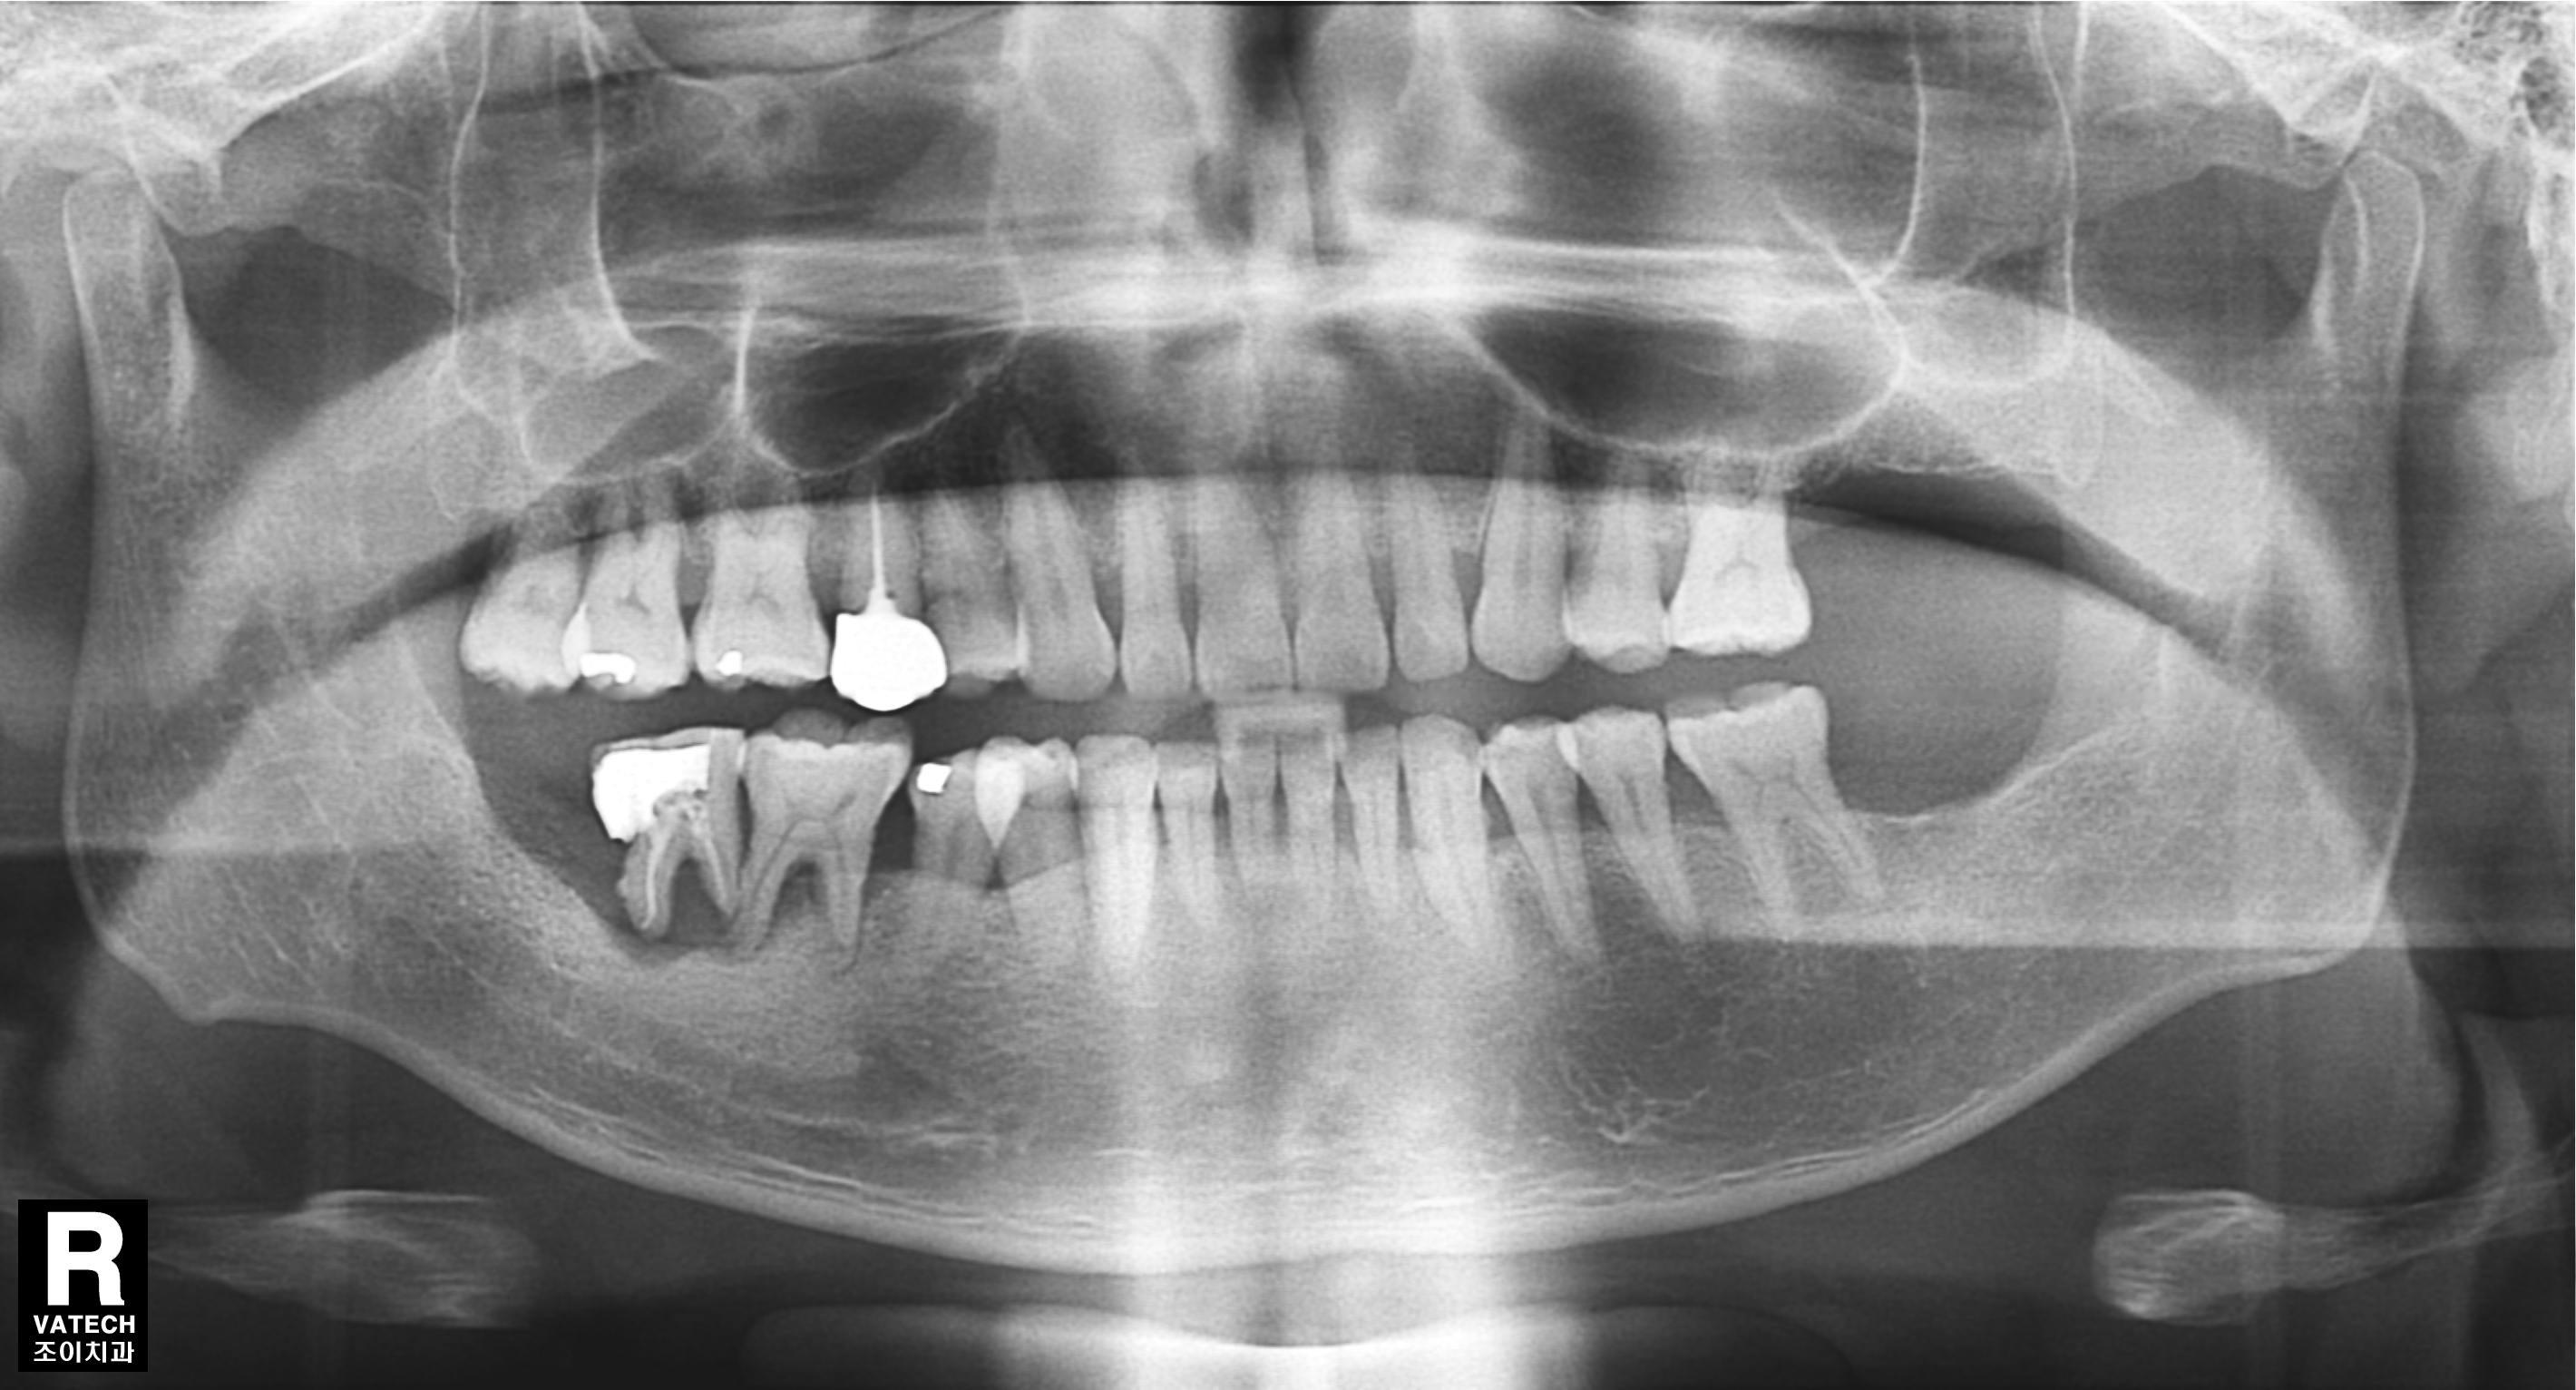

[임플란트] 제목 : 치주환자의 임플란트 보철치료

50대 치주환자의 임플란트치료.